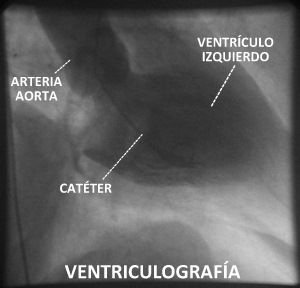

Cuando inyectamos contraste dentro de los ventrículos (lo que se denomina "ventriculografía"), habitualmente en el ventrículo izquierdo, podemos observar cómo se contrae el corazón, tanto de forma global como cada una de sus caras. De esta forma es posible ver zonas que no laten porque han sufrido un infarto en el pasado. También se puede estudiar la circulación de la sangre a través de las válvulas cardiacas, observando en ocasiones que no abren bien ("estenosis valvular") o que no cierran bien ("insuficiencia valvular").